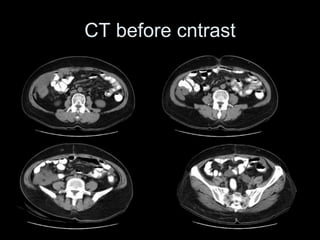

PMP : Diagnoses

• CT :

• Central displacement

of the small bowel and

compression of

retroperitoneal

structures

• Peritoneal cavity full of

PMP

CT before cntrast